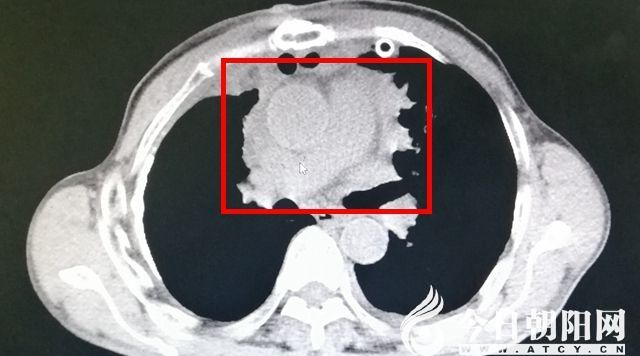

術(shù)前影像

患者李某(化名),因“呼吸費力伴咳嗽2個月”到市二院就診?;颊呖谑?個月前無誘因出現(xiàn)呼吸費力,活動后明顯加重,就診于當?shù)蒯t(yī)院,行對癥治療無明顯好轉(zhuǎn)。曾于赤峰某醫(yī)院行增強胸部CT檢查,提示為前縱隔囊實性占位,考慮惡性病變可能性大,因侵及心包、大血管,無法手術(shù),建議穿刺活檢保守治療。

近日,遼寧省朝陽市第二醫(yī)院胸外科在副院長白舒的帶領下,成功為一名61歲的男性患者實施了縱隔巨大腫瘤切除術(shù),腫瘤達30x15x10cm,并侵及心包、上腔靜脈、左無名靜脈、升主動脈及左右膈神經(jīng),手術(shù)風險和難度系數(shù)之高,實屬罕見。